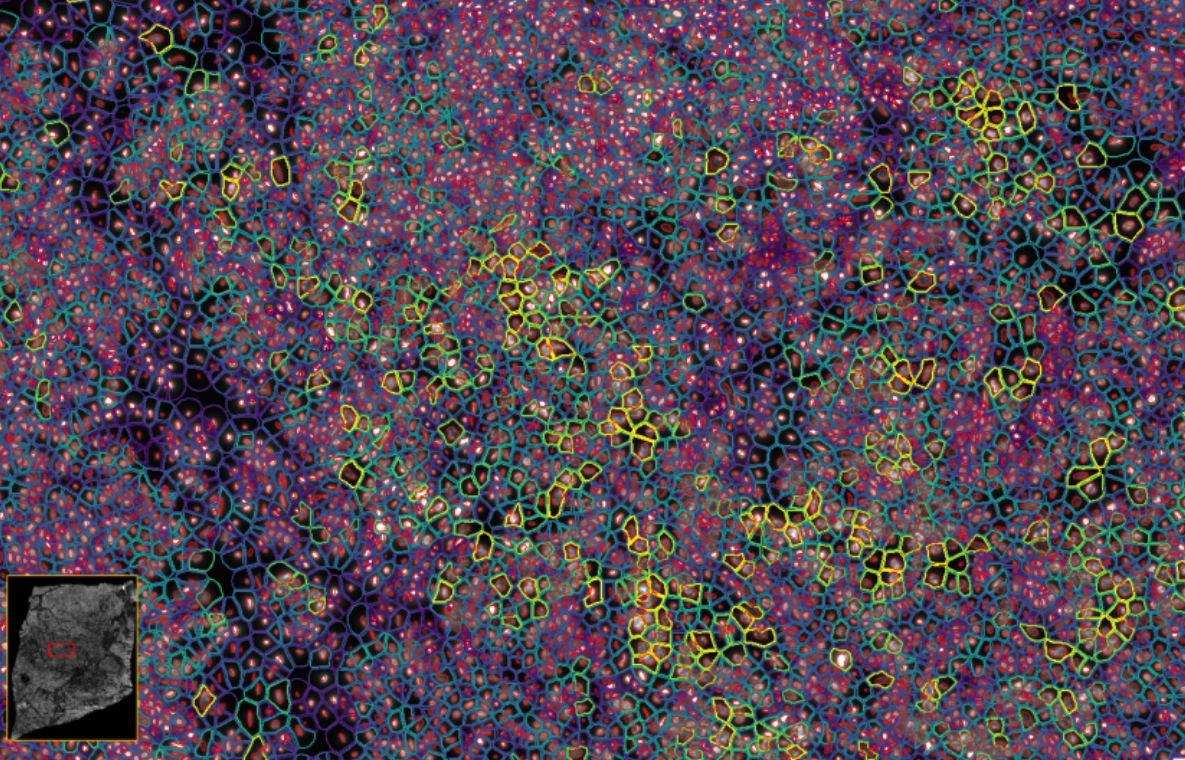

image.png

ͼ3£ºXenium½«¹âÑ§ÌØµã½âÂëΪת¼±¾±í°× £¬²É¼¯²¢ÐγÉͼÏñ